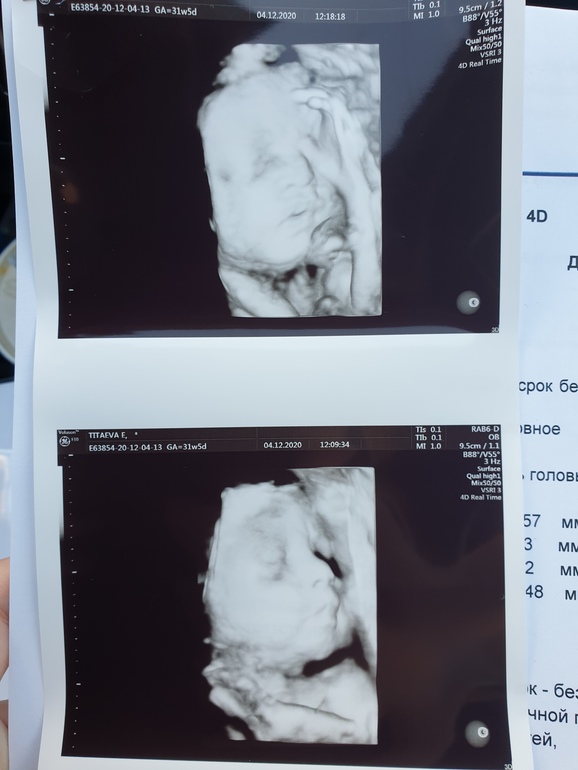

Наш третий скрининг 🥰 +фото

Прошли сегодня наконец-то 3 скрининг, потом доченьку увидим только после рождения 😊 Почему-то очень переживала, ночью даже плохо спала.

У малышки все хорошо, развитие правильное, все также стабильно отстаем на 1 недельку по срокам, по мес 31+5, по узи 30+5. Животик небольшой на 30 нед.ровно, и длина бедра по нижней границы нормы (не страшно же??) Стройненькая, как сказала врач. Но допплер отличный, а значит питания ей хватает. Вес примерно 1450гр. У кого какой вес у деток был на 30-31 недельке?

Ну и скину вам показать фоточку 😍